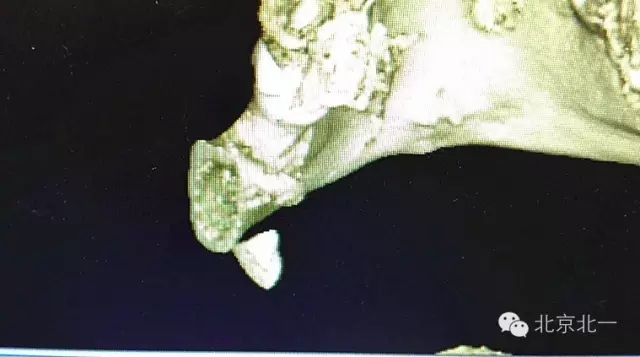

圖二:CBCT重建可見牙根位于舌側(cè)達到頜下間隙。

640.webp (6).jpg

圖三:BCBT重建可見牙根貼在下頜骨下緣舌側(cè)面,接近頜下間隙

640.webp (7).jpg